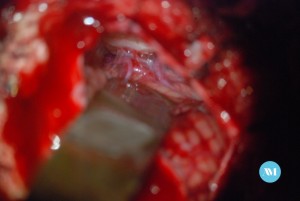

Algunos pacientes pueden requerir cirugía para aliviar la presión sobre el nervio. Las técnicas:

- Cirugía para extirpar un vaso sanguíneo que está ejerciendo presión sobre el nervio trigémino (llamada descompresión microvascular o DMV).